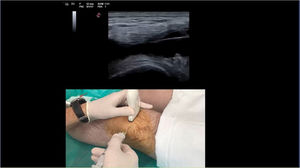

Throughout the procedure, the participant must resolve the questions that are posed to them, some of which are related to knowledge and others to decision-making (Fig. 6). We use images of synovial fluid in syringes, ultrasound images, as well as various preparations on slides to identify crystals using an optical microscope and cell cultures for microbiological analysis (Fig. 7).